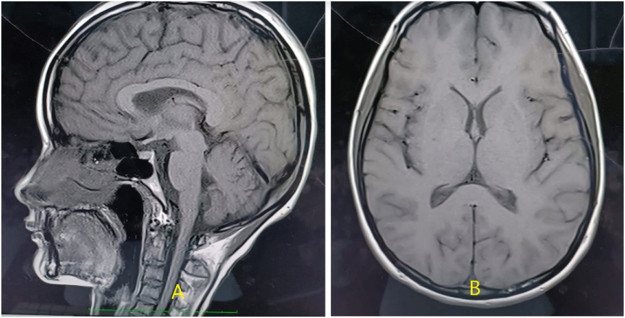

Case presentation: A 16-years-old female presented with long history of generalized weakness since age of 10 years, followed by bilateral sensorineural hearing loss, bulbar symptoms, and limb spasticity. Neurological examination revealed upper motor neuron signs in upper limbs, lower motor neuron signs in lower limbs, and bulbar involvement. Nerve conduction test was normal however, MRI showed early degenerative changes, and diagnosed with J-ALS after careful evaluation. She was started on Riluzole. Despite ICU care and supportive interventions including PEG and tracheostomy, she succumbed to respiratory failure.